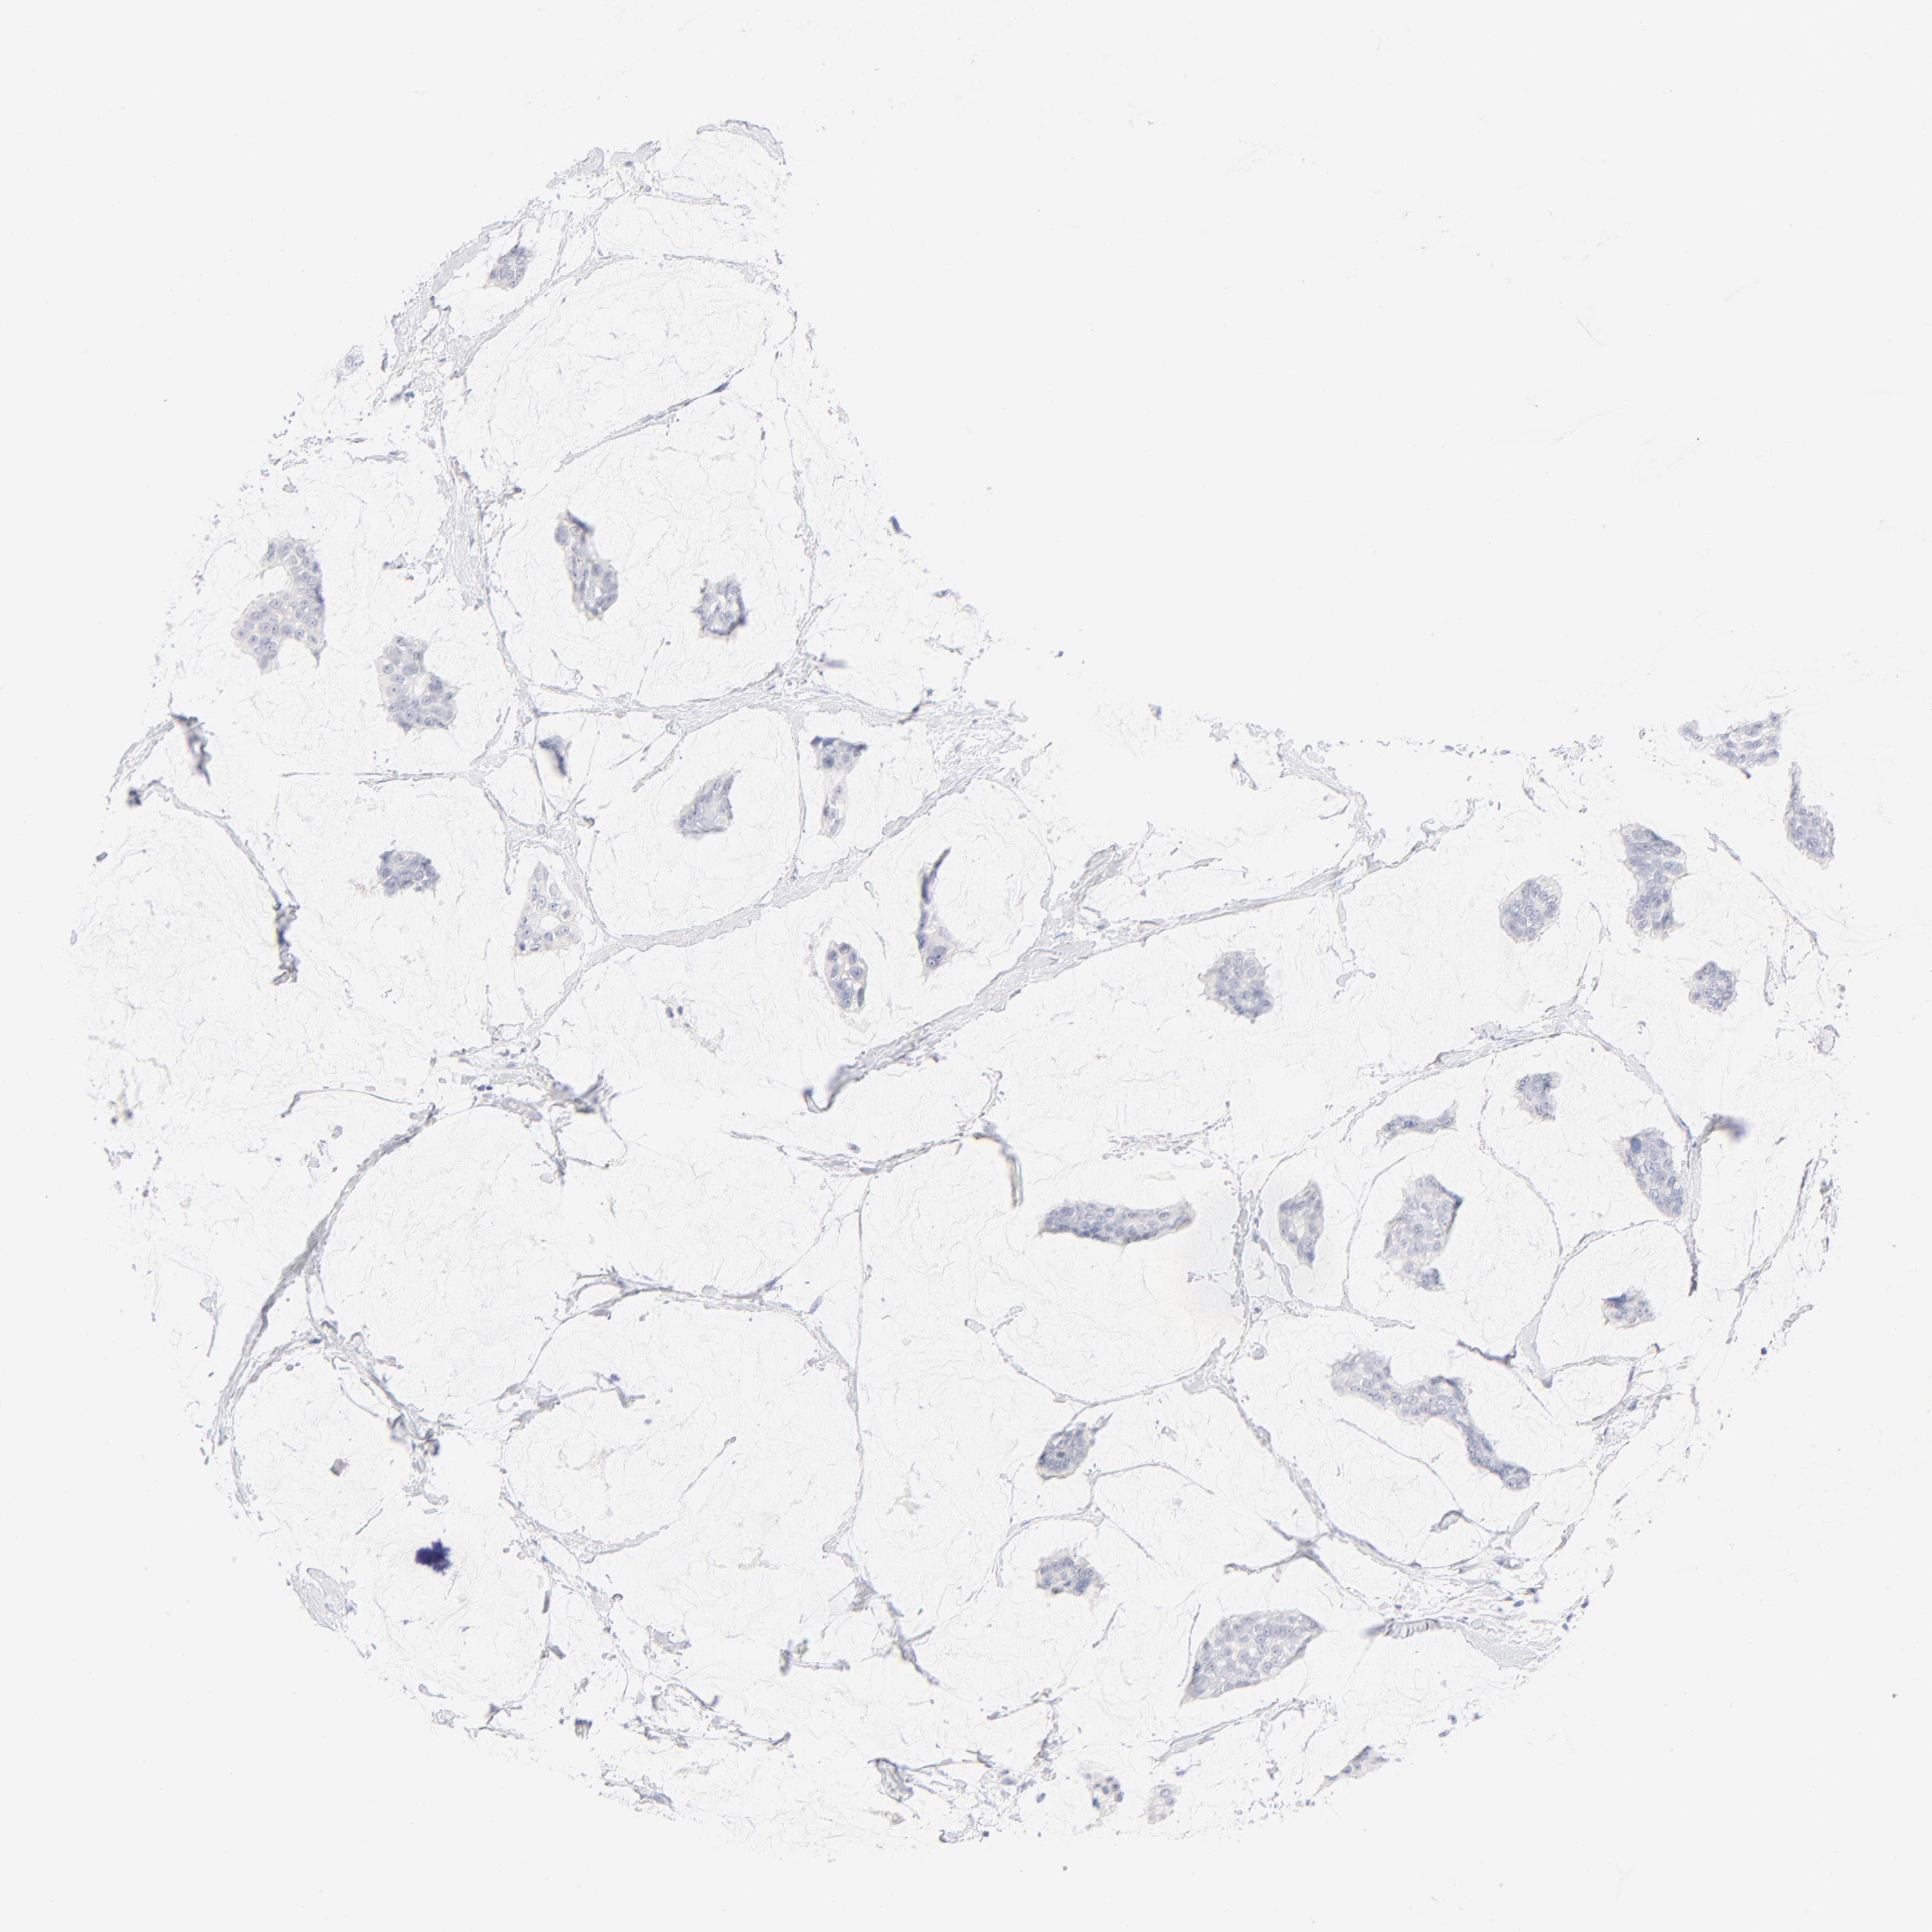

CANCER BREAST CANCER Show tissue menu

Breast cancer

Human cancer

Breast invasive carcinoma